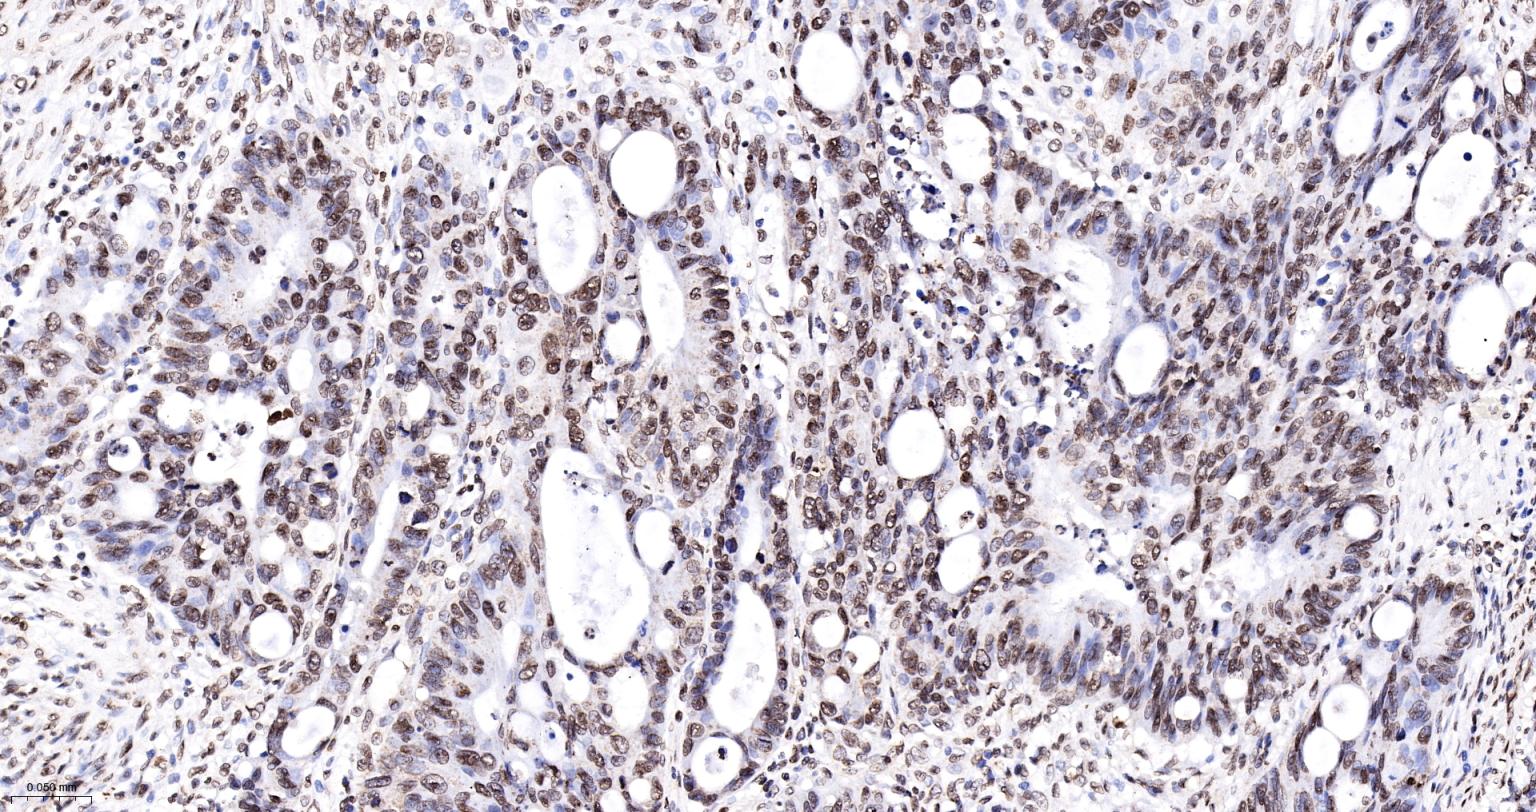

Paraformaldehyde-fixed, paraffin embedded Human Colon Cancer; Antigen retrieval by boiling in sodium citrate buffer (pH6.0) for 15 min; The section was incubated with phospho-SMC1 alpha (Ser957) Monoclonal Antibody, Unconjugated (bsm-62980R) at 1:200 overnight at 4°C, followed by conjugation to the bs-0295G-HRP and DAB (C-0010) staining.